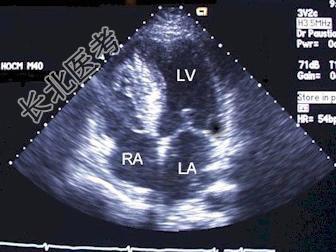

- 单项选择题心尖四腔切面,二尖瓣与三尖瓣的鉴别无误的是 ( )

A、二尖瓣位置高

B、二尖瓣前叶较短

C、三尖瓣位置高

D、三尖瓣前叶较长

E、三尖瓣隔叶较长